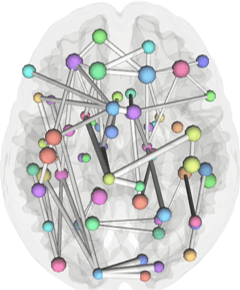

• Imaging Statistical Analysis

• Frequentist Statistics

• Bayesian Modelling

• Graph Theoretical Analyses

Network view of brain